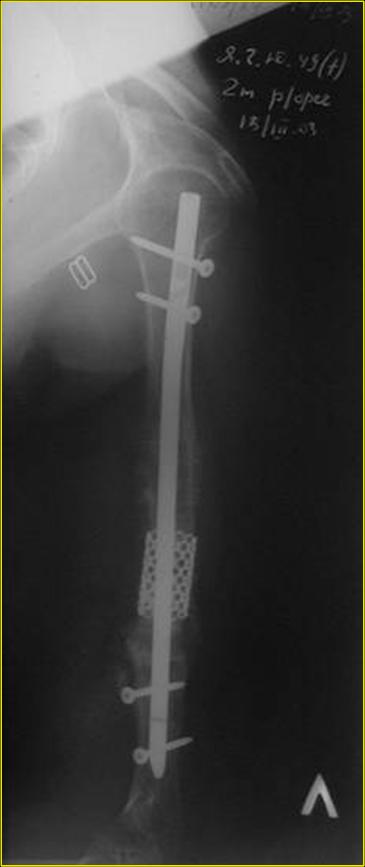

Типичная положительная ситуация для интрамедуллярного остеосинтеза с

использованием опорного металлокаркаса для компенсации дефекта.

Послеоперационное ведение активное или агрессивно-активное. Каркасы

можно заказать в МАТИ.

Рентгеновская версия реконструкции. хронология:

после операции, 2 мес. после операции, через 1 год

Движения в полном объеме восстановлены к 2 мес. после операции. Если надо могу показать мультик. Сейчас уже прошло более 3 лет, больная не

показывается. Успехов ЛАФ.